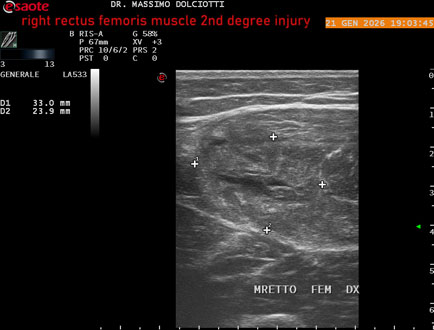

Data inserimento: 23/01/2026

Ecografia del: 21/01/2025

Strumento: Esaote MyLab Eight

Sonda: Lineare Multifrequenza 3-13 MHz

Età Paziente: M 23 anni

Motivazione dell'esame: dolore al terzo prossimale della coscia destra da tre giornii.

Commento all'esame: le immagini ed il video documentano, al terzo prossimale del muscolo retto femorale destro, area disomogenea, ipoecogena, delle dimensioni di 35 mm per uno spessore di 18 mm, misura ottenuta per asse corto o trasversale, e di 71 mm x 20 mm, misura ottenuta per asse lungo o longitudinale, da ricondurre a lesione muscolare di 2° grado con modica raccolta sieroematica intramuscolare.

Conclusioni: lesione di 2° grado del muscolo retto femorale destro (2nd degree injury of the right rectus femoris muscle).